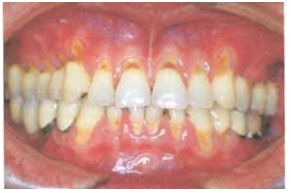

76 如下圖,患者四顆犬齒頰側已無附連牙齦,依 Miller 牙齦退縮分類屬第幾級? (A)Ⅰ (B)Ⅱ (C)Ⅲ (D)Ⅳ